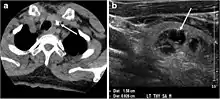

Fig. 1. An incidentally discovered colloid nodule with calcification, shown on CT scan of a 58-year-old female patient. a Non-enhanced axial CT scan of the neck demonstrates a coarse calcification at the left thyroid inferior pole. b Sagittal grey scale ultrasound of the thyroid demonstrates a heterogeneous nodule with a predominant cystic component. Calcification was not seen in the ultrasound, probably due to its lower location in the superior mediastinum.[1]

Fig. 2. A 51-year-old female patient post left hemithyroidectomy, with incidentally discovered a right thyroid colloid nodule on CT scan. an Enhanced axial CT scan of the neck demonstrates a well-defined, hypodense right thyroid nodule (white arrow) with no internal calcifications or cervical lymphadenopathy. b Transverse greyscale thyroid ultrasound demonstrates a well-defined, hypoechoic right thyroid lobe nodule with a central echogenicity including comet tail (ring down) artefacts (white arrow). No vascularity (not shown) or calcifications were detected.